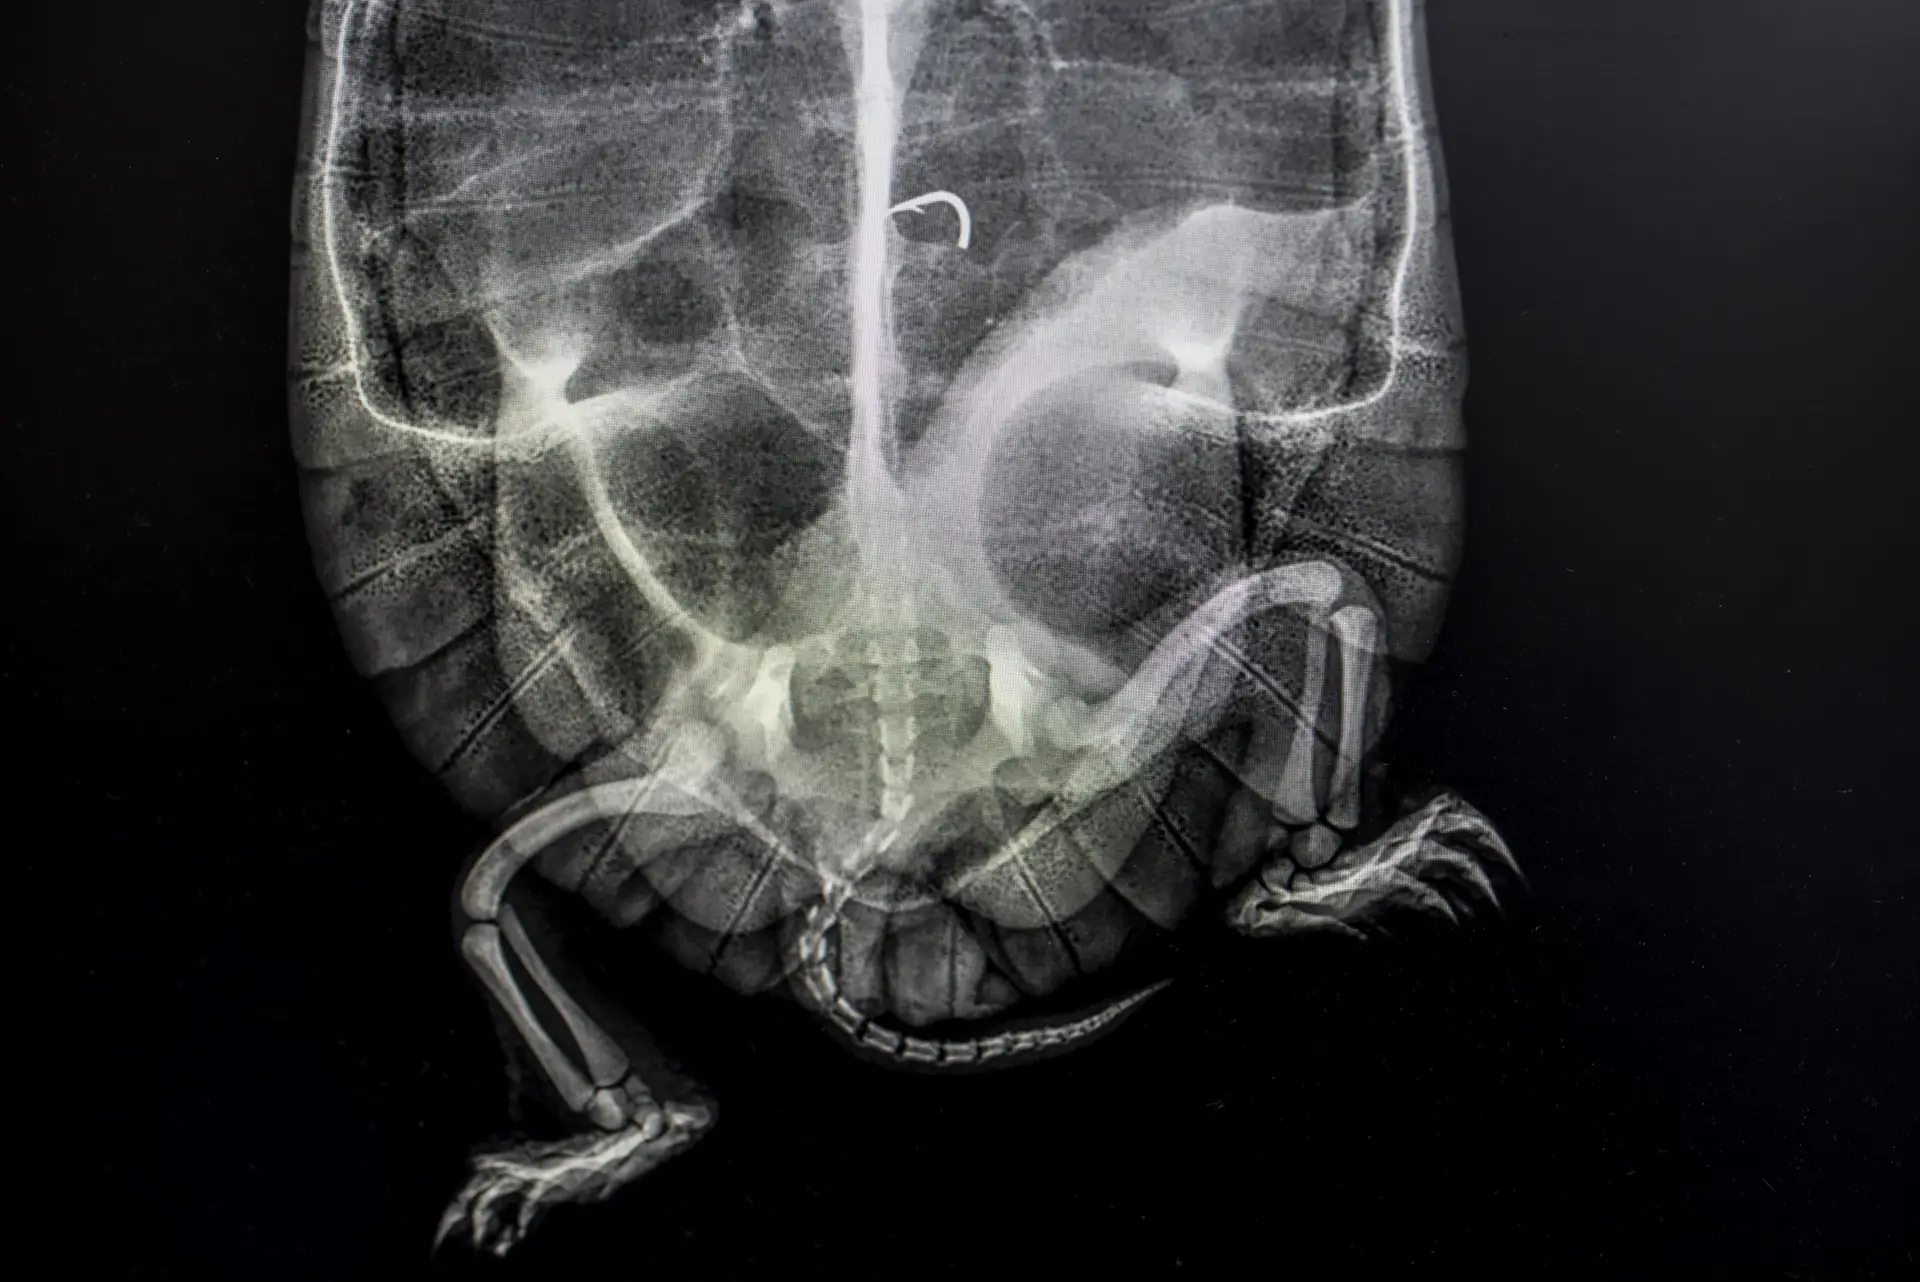

Continuing to search, officers also uncovered two taricaya turtles– a species native to the Amazon’s freshwater tributaries, categorised as “vulnerable” by conservationists – hidden in a concrete patio.